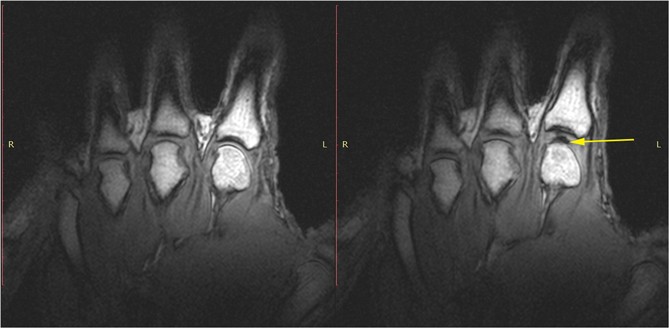

MRI掃描下的關節液中泡泡形成(箭頭處) photo credit: Reference#2 via Journal PLOSONE